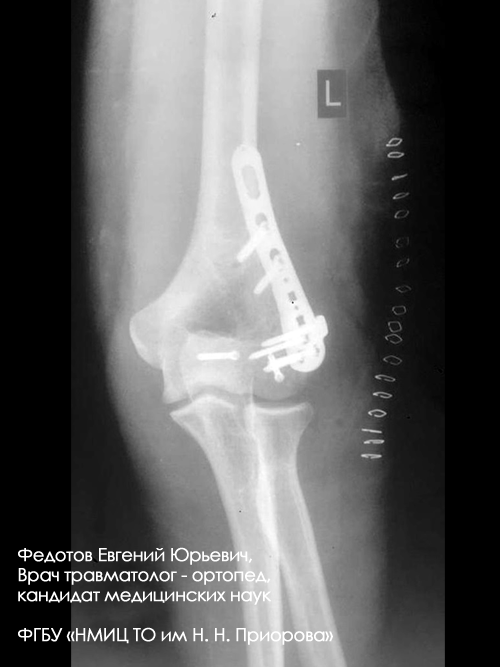

Пациентка с тяжелым внутрисуставным переломом нижнего отдела (мыщелков) плечевой кости с повреждением локтевого сустава.

Рентгенограмма до операции.

Выполнена операция: металлоостеосинтез плечевой кости пластинами LCP, анатомия локтевого сустава полностью восстановлена. Гипсовая повязка после операции не применялась, сразу разрешена разработка движений в суставах конечности.

Результат через 14 дней после операции. Швы только что сняты. Уже видна функция конечности, достаточная для обслуживания себя в быту.

Результат через 3 мес. после операции. Функция конечности полностью восстановлена.